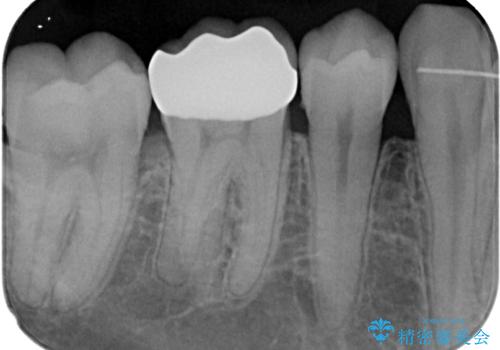

- 銀歯をセラミックにしたいとのことで来院された患者様です。検査の結果、メタルインレーが大きくご自身の歯の残る量を考慮して、オールセラミッククラウンによる補綴治療を行っていくことにしました。

拡大鏡視野下で、メタルインレー、虫歯の除去を行いオールセラミッククラウンに適した形に整えました。

歯と歯茎の間に圧排糸と言われる糸を入れてシリコーン印象材にて型どりをしました。

違和感もなく、適合性も良い被せものを入れることができました。

適合の高い被せものを入れることにより再び虫歯になるリスクを下げることができます。